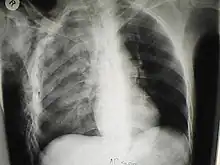

Bubbles of air in the subcutaneous tissue (arrow) feel like mobile nodules that move around easily

A chest X-ray of a right sided pulmonary contusion associated with flail chest and subcutaneous emphysema